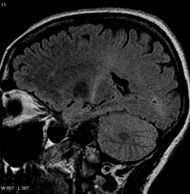

| MRI (parasagittal FLAIR) demonstrates increased T2 signal within the posterior part of the internal capsule and can be tracked to the subcortical white matter of the motor cortex, outlining the corticospinal tract, consistent with the clinical diagnosis of ALS | |